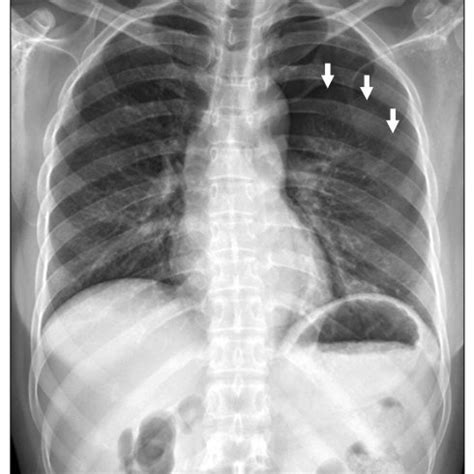

Posterolateral view of the chest demonstrating partial collapse of the